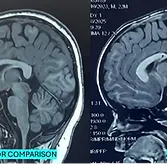

This eight year old boy complains of headache, lasting for last 3 months. No history of trauma. CNS exam including fundus was normal. Locallized tenderness noticed on the parietal side. No swelling. CT skull is enclosed

1. Radiological finding